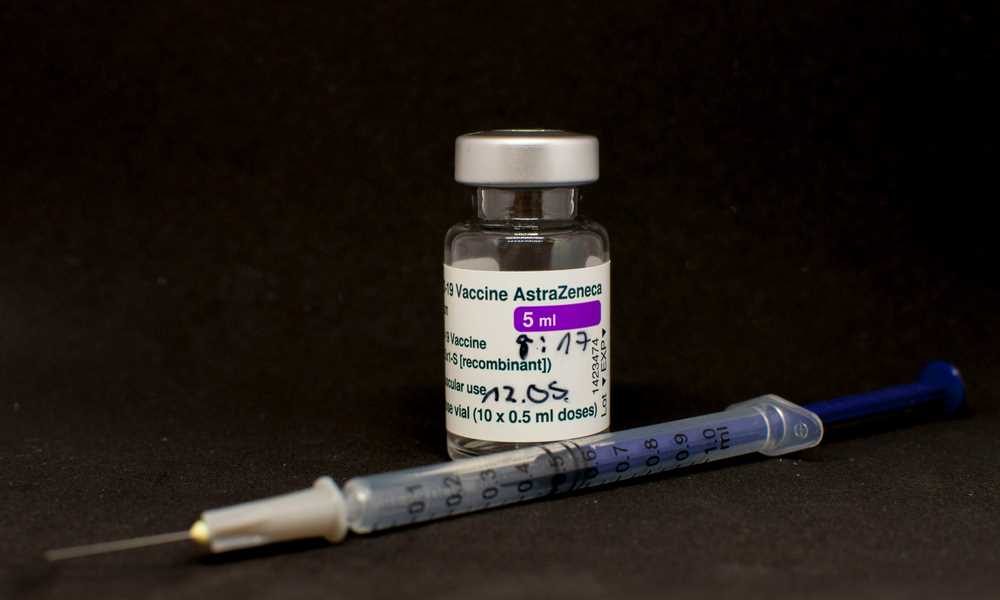

Europejska Agencja Leków (EMA) wydała w piątek zalecenie, w którym odradza stosowanie szczepionki firmy AstraZeneca przeciw Covid-19 u osób z rzadką chorobą naczyń krwionośnych - zespołem...

W szpitalu w Genui na północy Włoch zmarła w czwartek 18-latka, która 25 maja została zaszczepiona przeciw Covid-19 preparatem AstraZeneca - podały służby medyczne. Przeszła operację...